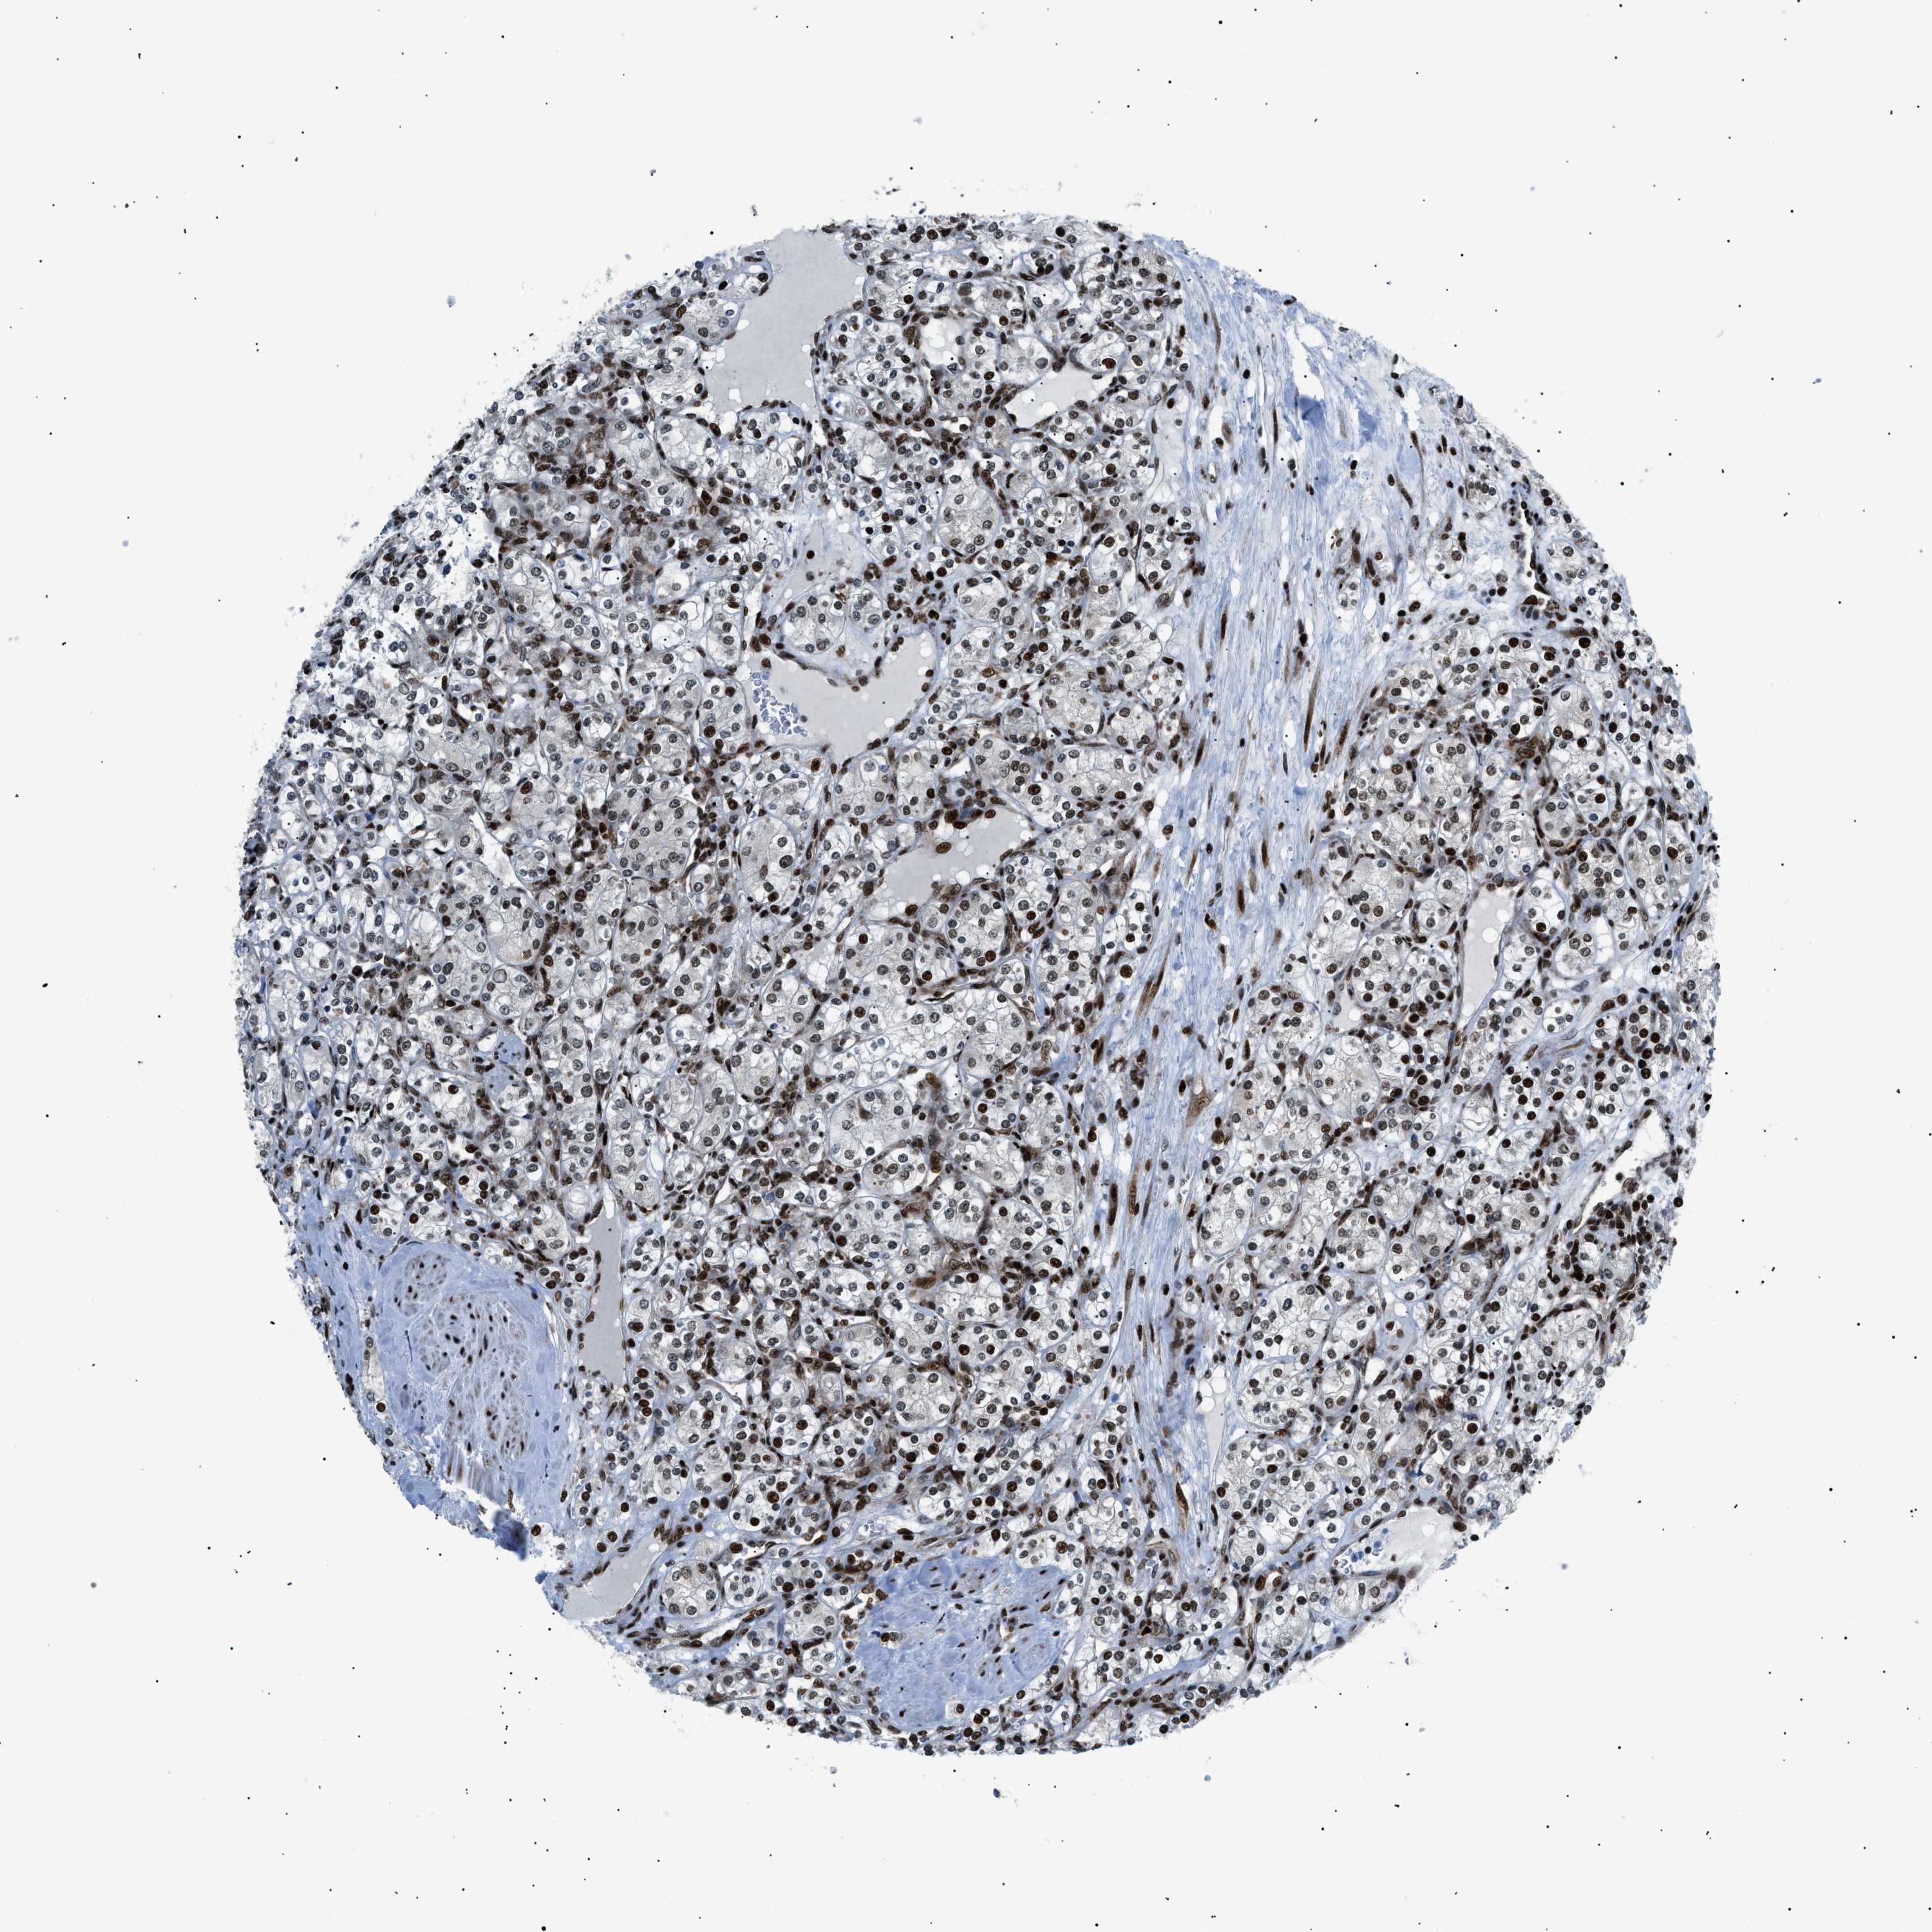

KIDNEY RENAL PAPILLARY CELL CARCINOMA (TCGA) - Interactive survival scatter ploti

The Survival Scatter plot shows the clinical status (i.e. dead or alive) for all individuals in the patient cohort, based on the same data that underlies the corresponding Kaplan-Meier plots. Patients that are alive at last time for follow-up are shown in blue and patients who have died during the study are shown in red.

The x-axis shows the expression levels (FPKM) of the investigated gene in the tumor tissue at the time of diagnosis. The y-axis shows the follow-up time after diagnosis (years). Both axes are complimented with kernel density curves demonstrating the data density over the axes. The top density plot shows the expression levels (FPKM) distribution among dead (red) and alive patients (blue). The right density plot shows the data density of the survived years of dead patients with high and low expression levels respectively, stratified using the cutoff indicated by the vertical dashed line through the Survival Scatter plot. This cutoff is automatically defined based on the FPKM cutoff that minimizes the p-score. The cutoff can be changed by dragging the vertical line or by entering a cutoff value in the square labeled "Current cut-off".

Under the Survival Scatter plot the p-score landscape (black curve; left axis) is shown together with dead median separation (red curve; right axis). Dead median separation is the difference in median mRNA expression between patients who have died with high and low expression, respectively. It is calculated as follows: median FPKM expression of dead patients with high expression - median FPKM expression of dead patients with low expression. This is intended to aid the user in visually exploring custom cutoffs and the associated p-scores and dead median separation.

Individual patient data is displayed and can be filtered by clicking on one or more of the category buttons on the top of the page. Categories describing expression level and patient information include: high, low, alive, dead, female, male and tumor stages. The scale of the x-axis can be toggled between linear and log-scale by clicking on the "x log" button. Mouse-over function shows TCGA ID, patient information and mRNA expression (FPKM) for each patient.

& Survival analysisi